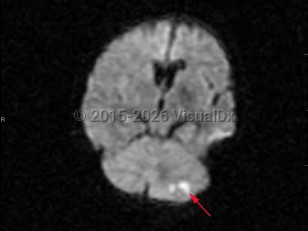

- Ischemic cerebellar strokes are predominantly either thrombotic or embolic. Thrombotic strokes are often caused by atherosclerosis, while embolic strokes are commonly cardiogenic (atrial fibrillation), septic, or due to coagulopathy.

Risk factors for cerebellar strokes are the same as for other cerebrovascular pathologies: hypertension, hyperlipidemia, diabetes, cardioembolic risks such as atrial fibrillation, and tobacco abuse are chief among them. Cerebellar hemorrhages can also be caused by a rupture of vascular malformations; hereditary hemorrhagic telangiectasia (HHT) is a particular risk factor. Rupture of vascular malformations is a more likely cause in children. Other risk factors for cerebellar hemorrhages include sympathomimetic abuse such as cocaine use. Increased urinary sodium is associated with increased risk.